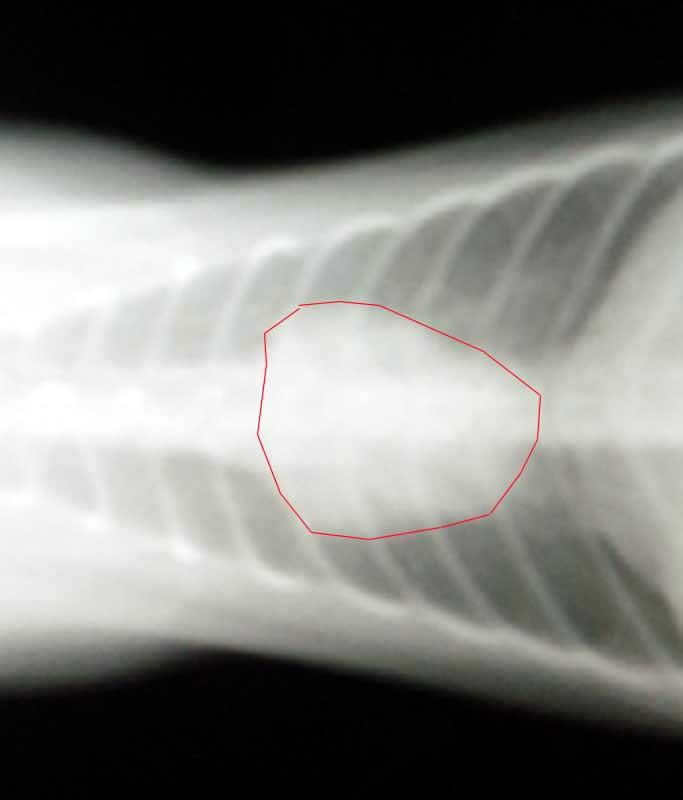

拡大すると・・なんとなくハート型のような感じです。

心臓がハート型になるとバレンタインハートと言って「猫の肥大型心筋症」の疑いがあります。